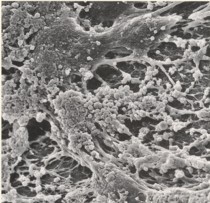

口腔内の2大疾患であるむし歯・歯周病が細菌による感染症であることは広く知られています。口腔内常在細菌の集合体をデンタルプラークと言ってきました。今日では歯面に強固に付着したデンタルプラークはバイオフィルムと言い換える事ができます。(左図:口腔内プラーク)

デンタルプラークは単に細菌の集合体としての概念でしたが、バイオフィルムは菌と菌が生産する多糖体の複合体との概念です。多糖体はバリヤーや運搬経路の役割を果たし、環境変化や科学物質から内部の細菌を守っています。その中では嫌気性菌から好気性菌まで様々な種類の細菌が存在し、情報伝達を行いながらコミュニティを形成しています。こうして、細菌生息密度の高い閉鎖的なコロニーが形成され、恒常性が保たれています。(右図:デンタルプラークの電子顕微鏡)